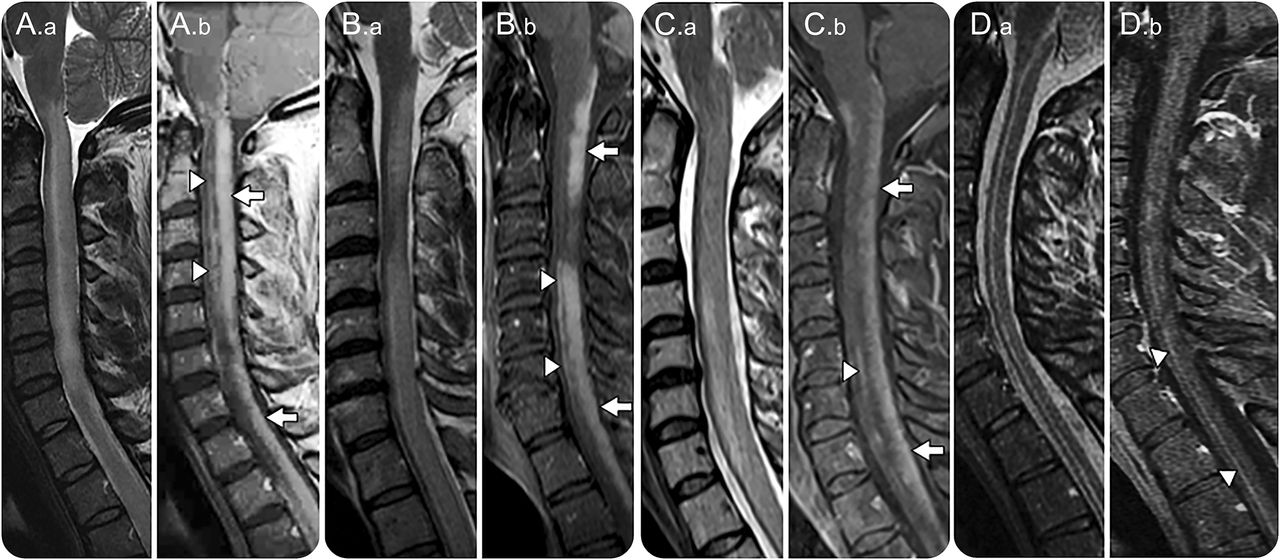

核磁共振成像显示纵向广泛的T2 hyperintensity (。a、B。a, C。,地方检察官)和背单纯增强(a。b, b。b, C。b; arrows) and central canal enhancement (A.b, B.b, C.b, D.b; arrowheads).